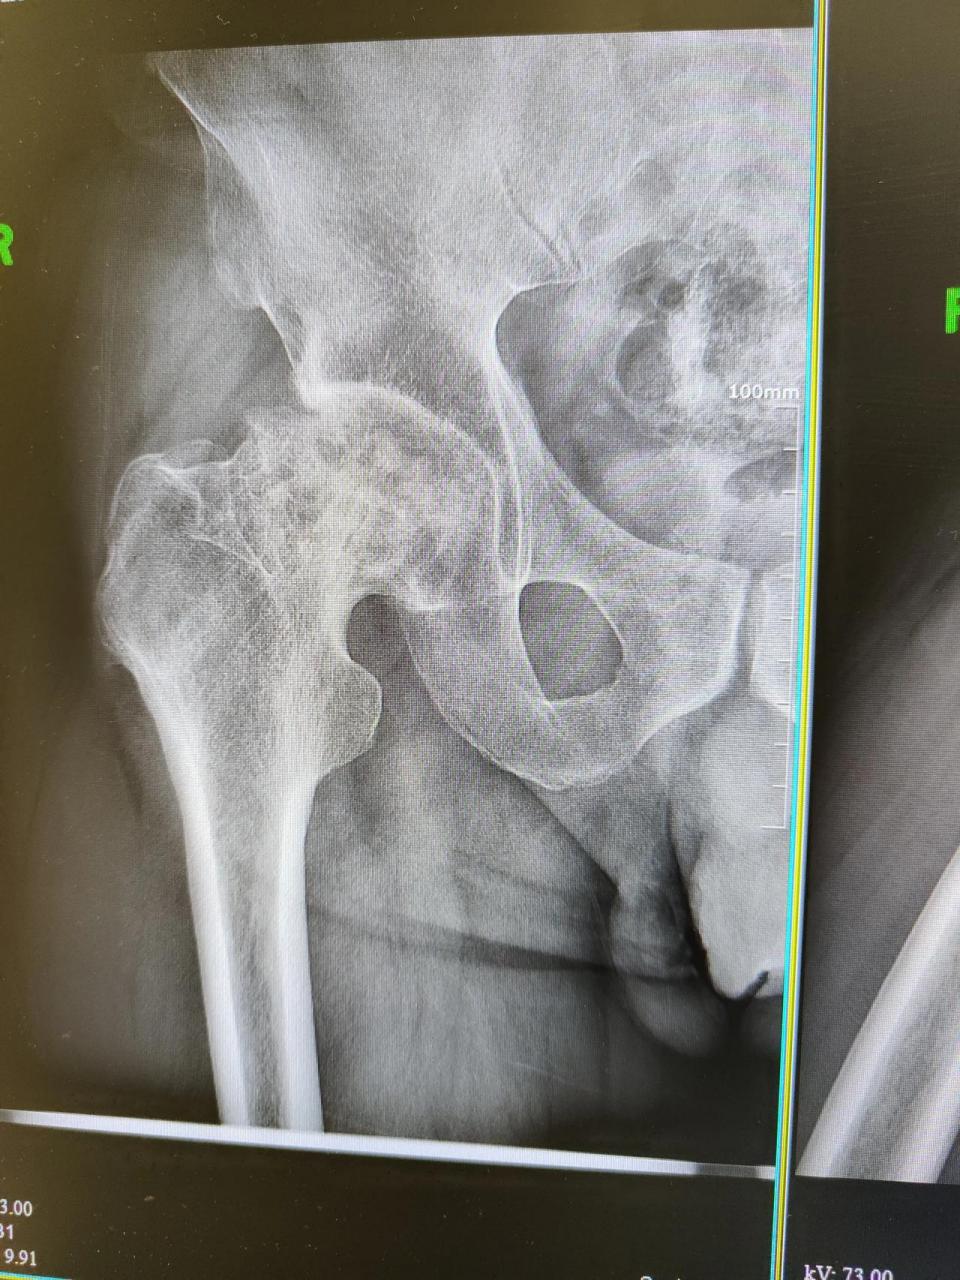

股骨头坏死

北京患者股骨头坏死的图片.第一张,第二张拍照于2023年6月26日.

图片尺寸960x1280